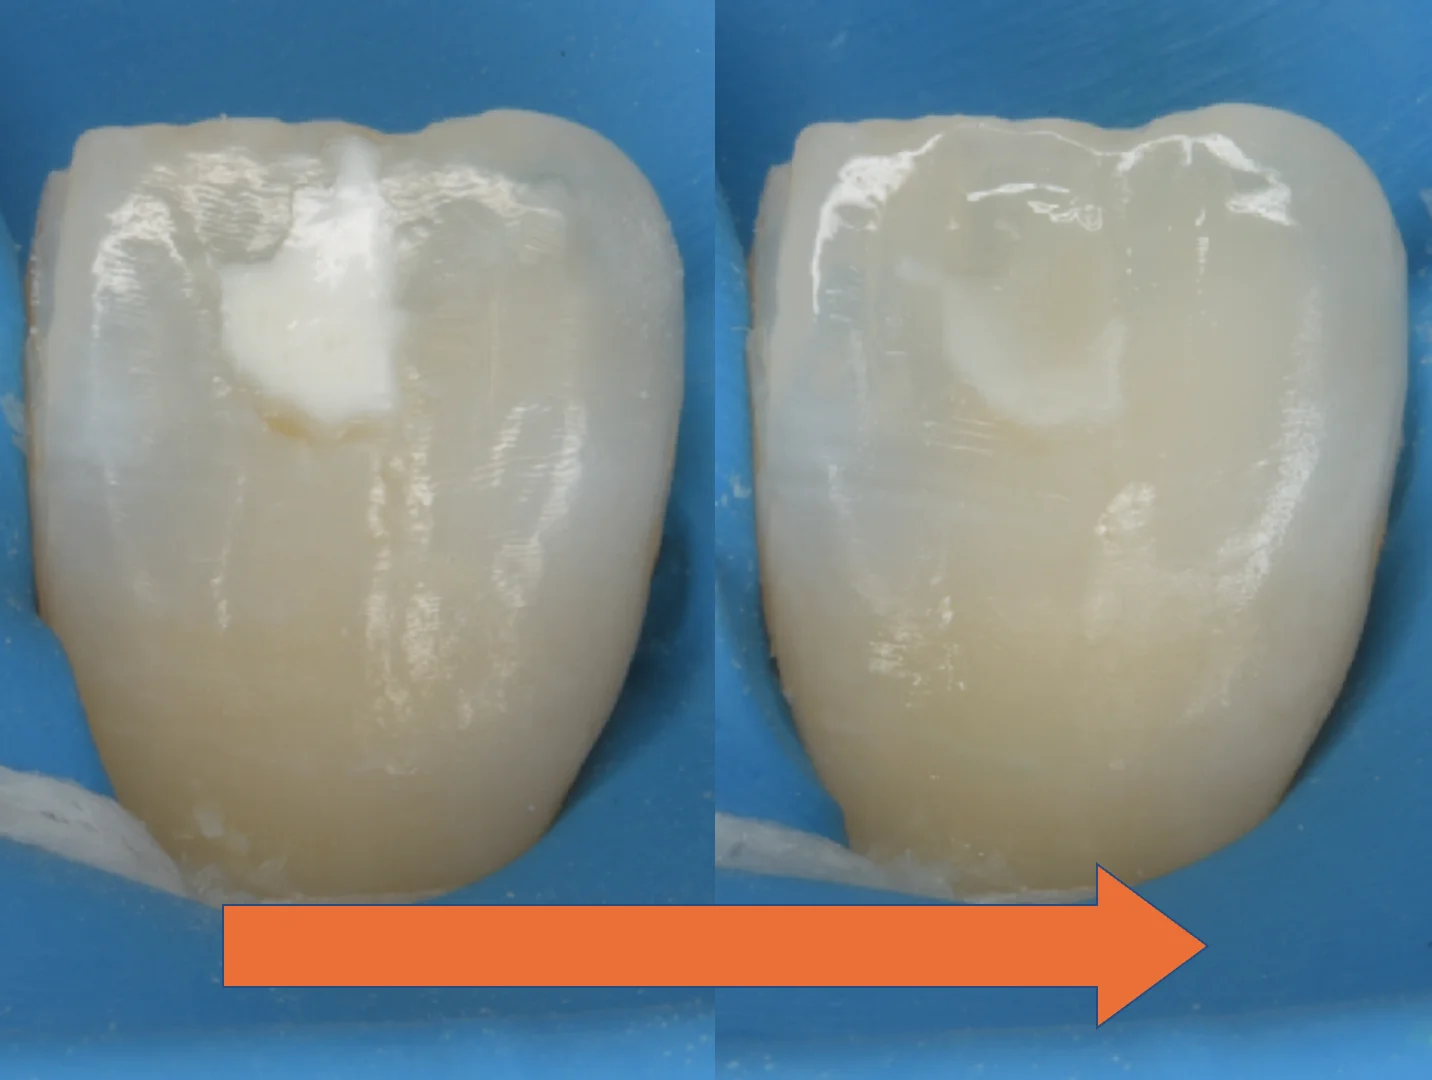

こちらがICONにて処置を行った直後の写真になります。

大分薄くはなっていますが、それでもうっすらと残存しているのがわかると思います。

ICON治療の際に使用する強い薬剤から歯肉を守るためにつけていたゴムのマスクを外して術前術後で反転して見やすくしたのがこちらになります。

随分と目立たなく、違和感がなくなったのが分かるかと思います。